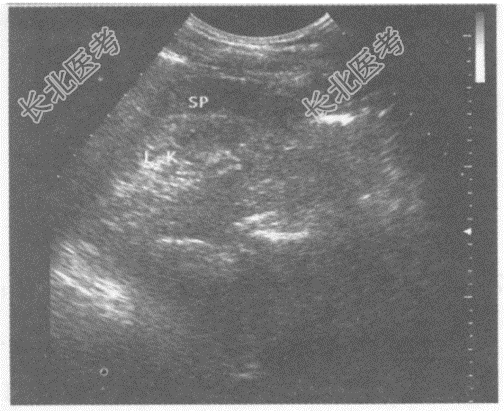

- 单项选择题临床资料:女, 55岁,自述腰痛1年余, 近日尿量减少。

临床物理检查:肾区叩痛。

化验检查: 尿肌酐增高,尿蛋白4+。

超声综合描述: 双肾表面不平,大小正常, 皮质回声增强,皮髓界限不清, 集合系统结构紊乱。

超声提示: A、双肾皮质回声增强

B、双肾萎缩

C、双肾正常声像图

D、双肾弥漫性病变

E、双肾皮质无回声